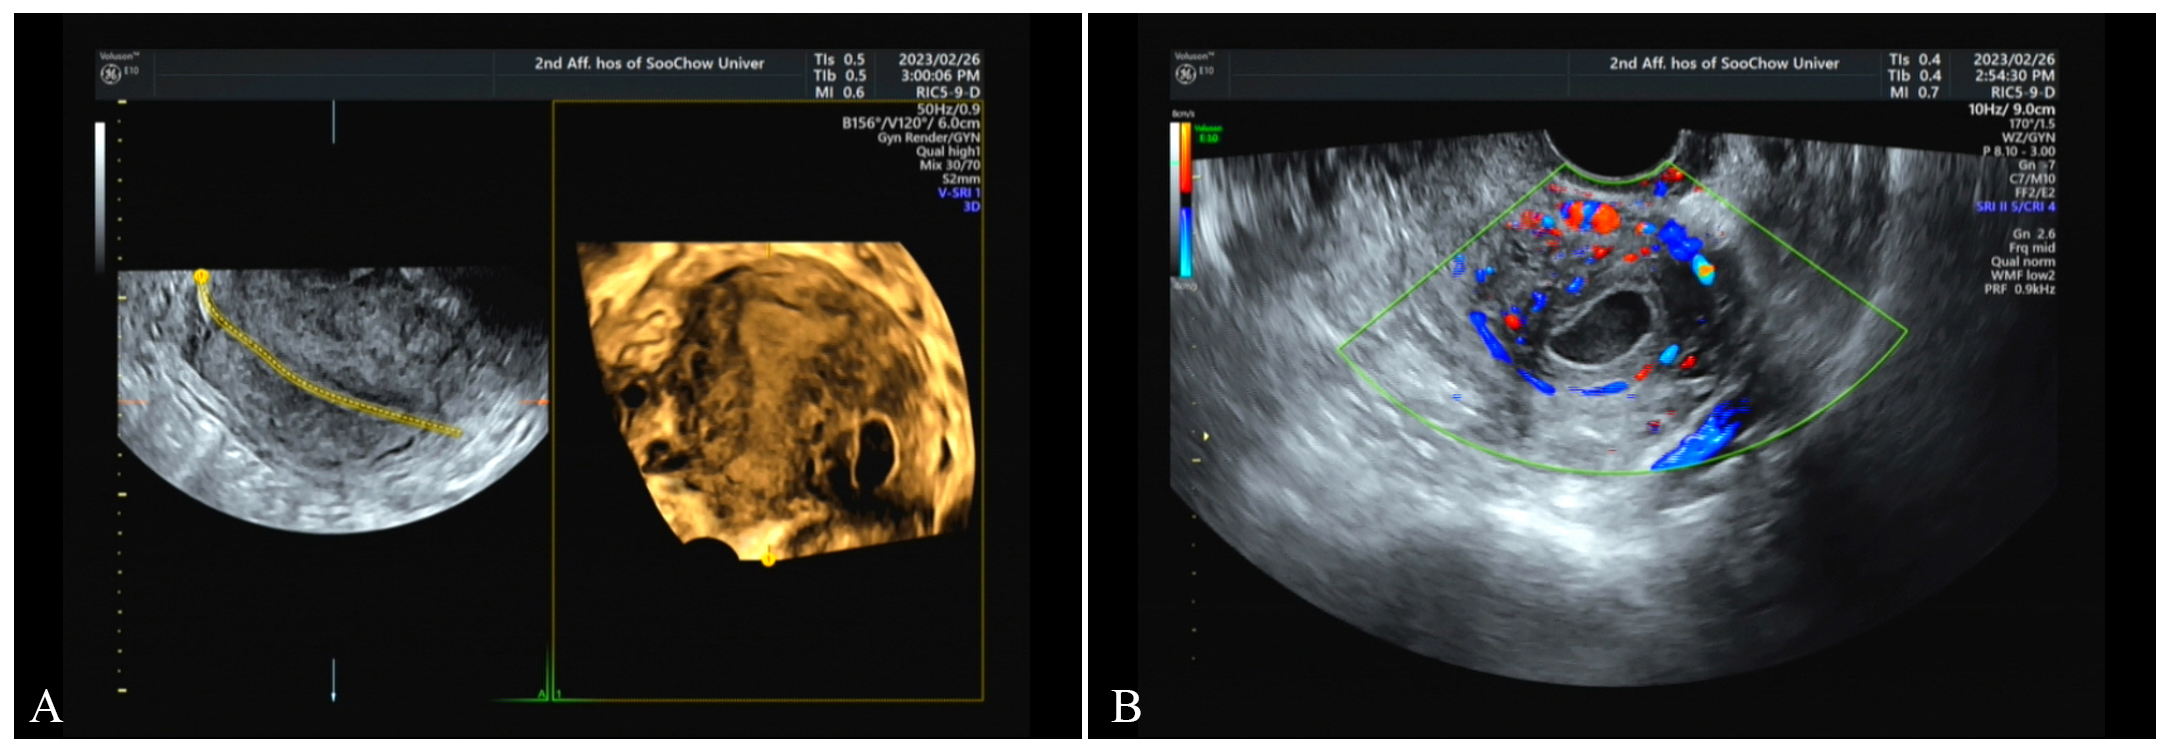

Fig. 1. On February 26, transvaginal ultrasound scan. (A) A gestational sac was seen near the uterine angle, measuring approximately 21 mm